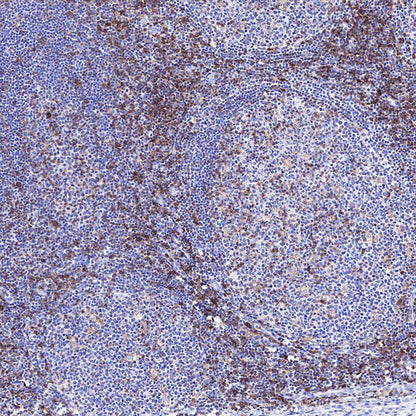

IHC shows positive staining in paraffin-embedded human mantle cell lymphoma. Anti-CD43 antibody was used at 1/1000 dilution, followed by a HRP Polymer for Mouse & Rabbit IgG (ready to use). Counterstained with hematoxylin. Heat mediated antigen retrieval with Tris/EDTA buffer pH9.0 was performed before commencing with IHC staining protocol.